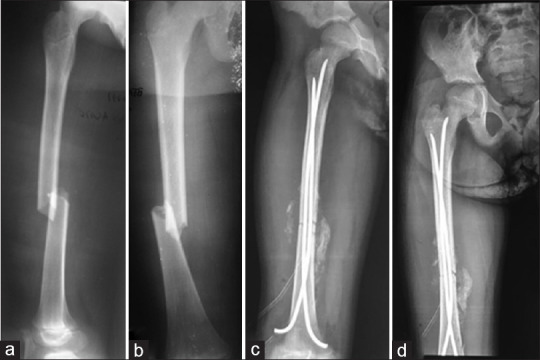

Results: Sixty-two patients underwent ESIN, of whom 44 patients (70.96%) were for femur fractures, nine patients (14.52%) for tibia and fibula fractures and nine patients (14.52%) for humerus fractures. The majority of the patients treated with ESIN were children older than 6 years. Nine patients (14.51%) and 13 patients (20.98%) underwent ESIN following polytrauma and multiple fractures, respectively. Seven patients (11.29%) were operated on through-closed ESIN method. The unavailability of image intensifier (38.71%) and the presence of bone callus (40.32%) were the major reasons for using the open ESIN method. Thirty-three patients (53.23%) had minor or major complications. The majority of patients had satisfactory therapeutic outcomes.

Conclusion: ESIN gives good results, even when the fracture site is approached.